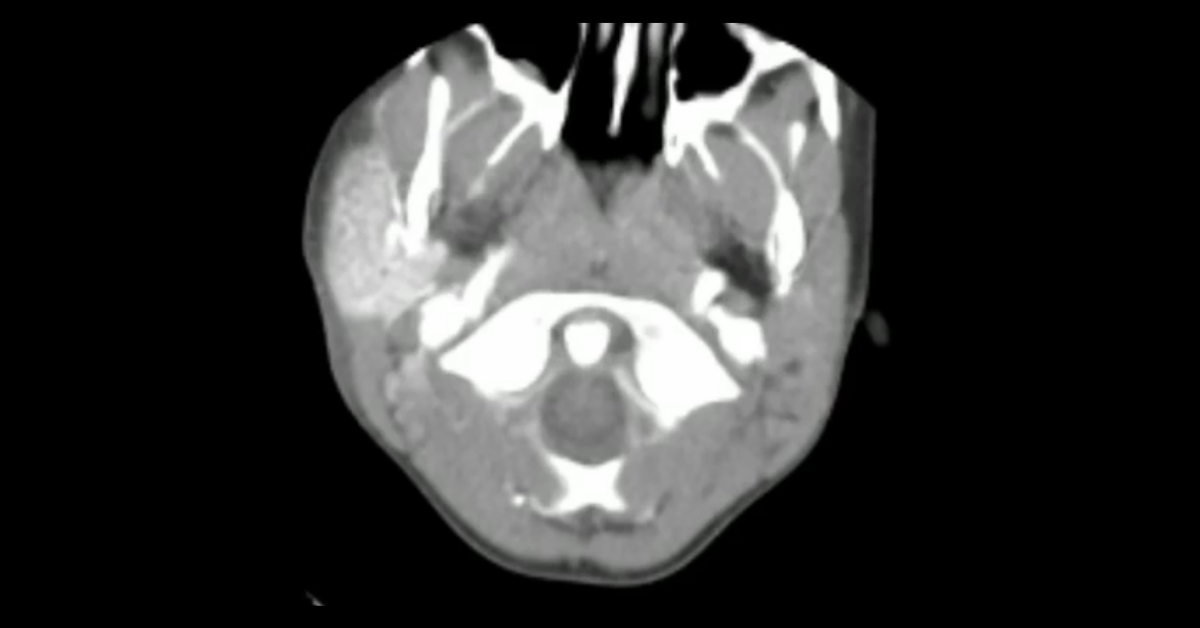

Pediatric Head & Neck CT

Cases of pediatric head and neck pathology, including abusive trauma and congenital abnormalities.